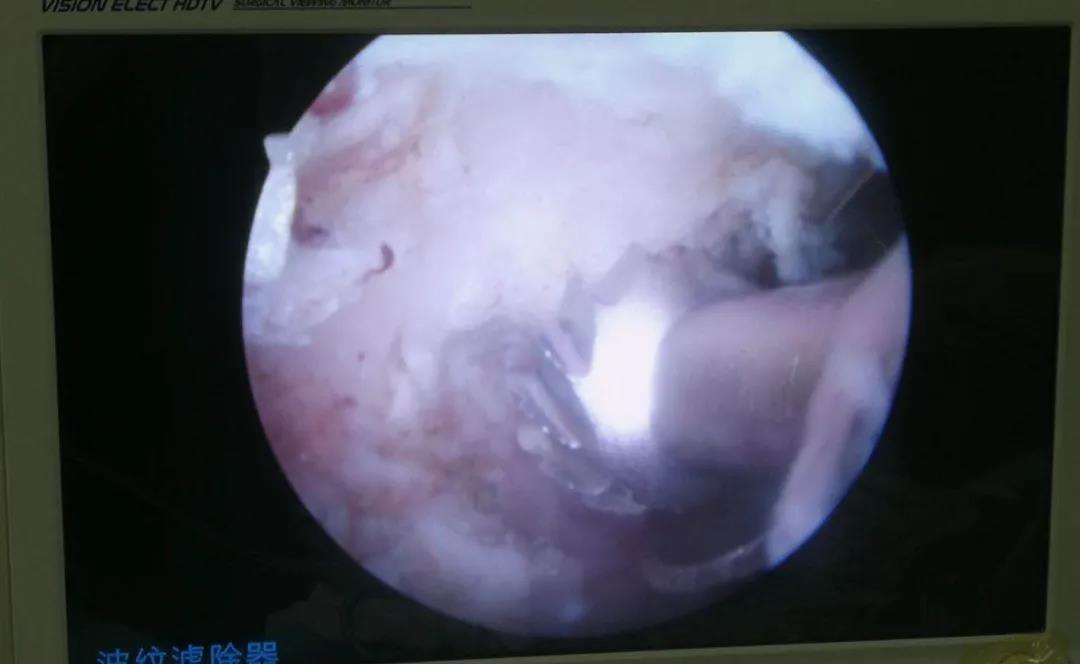

鏡下動(dòng)力磨削椎板

椎板鉗清理椎板及黃韌帶

顯露硬膜及神經(jīng)根

保護(hù)拉鉤牽開神經(jīng)根暴露突出鈣化的椎間盤

髓核鉗清除突出鈣化的椎間盤